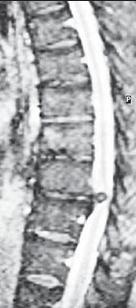

На серии МРТ № 26 наблюдаются секвестрированные грыжи межпозвонковых дисков в поясничном отделе позвоночника в сегментах LIV—LV LV—SI с каудальной (каудальной — расположенной ближе к нижней части туловища, направленной вниз) миграцией секвестра (фрагментов межпозвонкового диска) МРТ № 27 ![]() На серии МРТ № 27 наблюдаются секвестрированные грыжи межпозвонковых дисков в поясничном отделе позвоночника в сегментах L]-Sl с краниальной (вверх) миграцией секвестра (фрагментов межпозвонкового диска) Должен заметить, что по моим наблюдениям, к сожалению, практически все существующие на сегодняшний день методы лечения дегенеративно-дистрофического процесса, в том числе и осложнённого грыжами межпозвонковых дисков, направлены на устранение болевого синдрома. Проще говоря, лечат следствие, а не причину! Обращаю ваше внимание на следующий факт. Бывают грыжи межпозвонковых дисков, которые не вызывают никакой симптоматики, так называемые «немые» грыжи. Как правило, они имеют срединную локализацию. Некоторые «специалисты», практикующие в области вертебрологии, ошибочно считают, что такие грыжи абсолютно безопасны и лечить их нет необходимости. При этом навязывают своё (в данном случае необоснованное, ошибочное) мнение, что межпозвонковые грыжи опасны лишь тогда, когда вызывают боли. К сожалению, это далеко не так! МРТ № 28